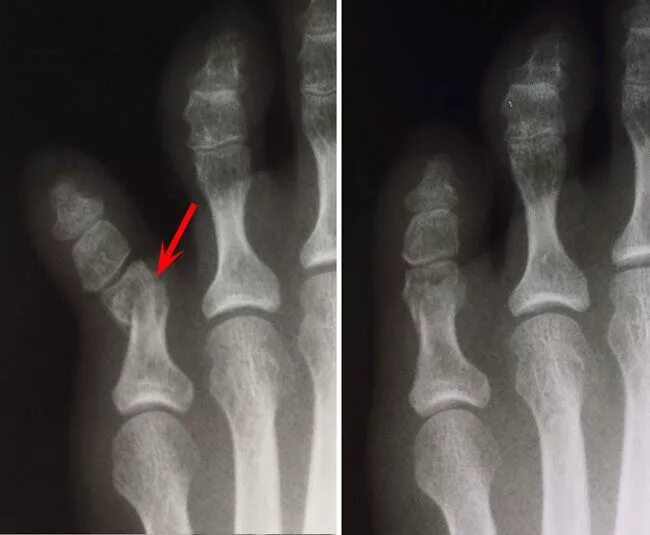

Трещина в кости ноги сколько